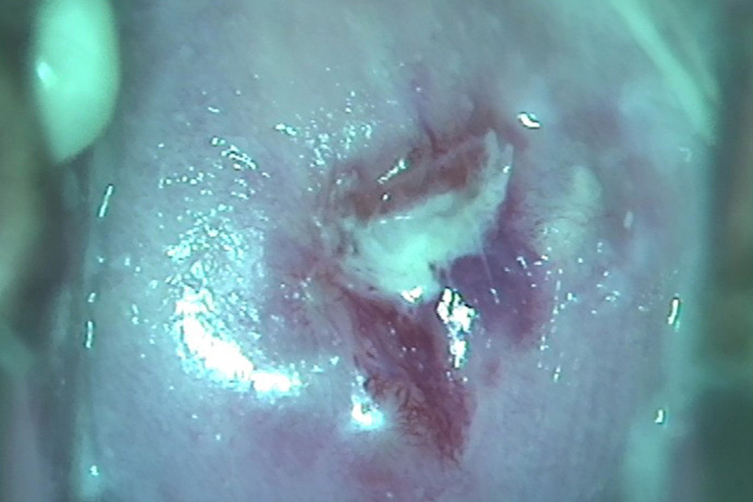

女性患者受到HPV病毒感染后,白带异常表现为多种形式。患者出现可白带增多、变黏、变脓等,或发现白带颜色偏黄,有腥臭味或其他异味。除白带异常外,患者生殖器部位可见细小的淡红色丘疹,起初丘疹数量较少,随着时间不断增加,丘疹数量逐渐增多,且不断变大,丘疹表面有明显隆起,这些隆起质地脆且坚硬,若尝试击破,患者有明显疼痛感。到后期生殖器可出现疣状增生,疣体形态多样,有鸡冠状、菜花状、乳头状等。